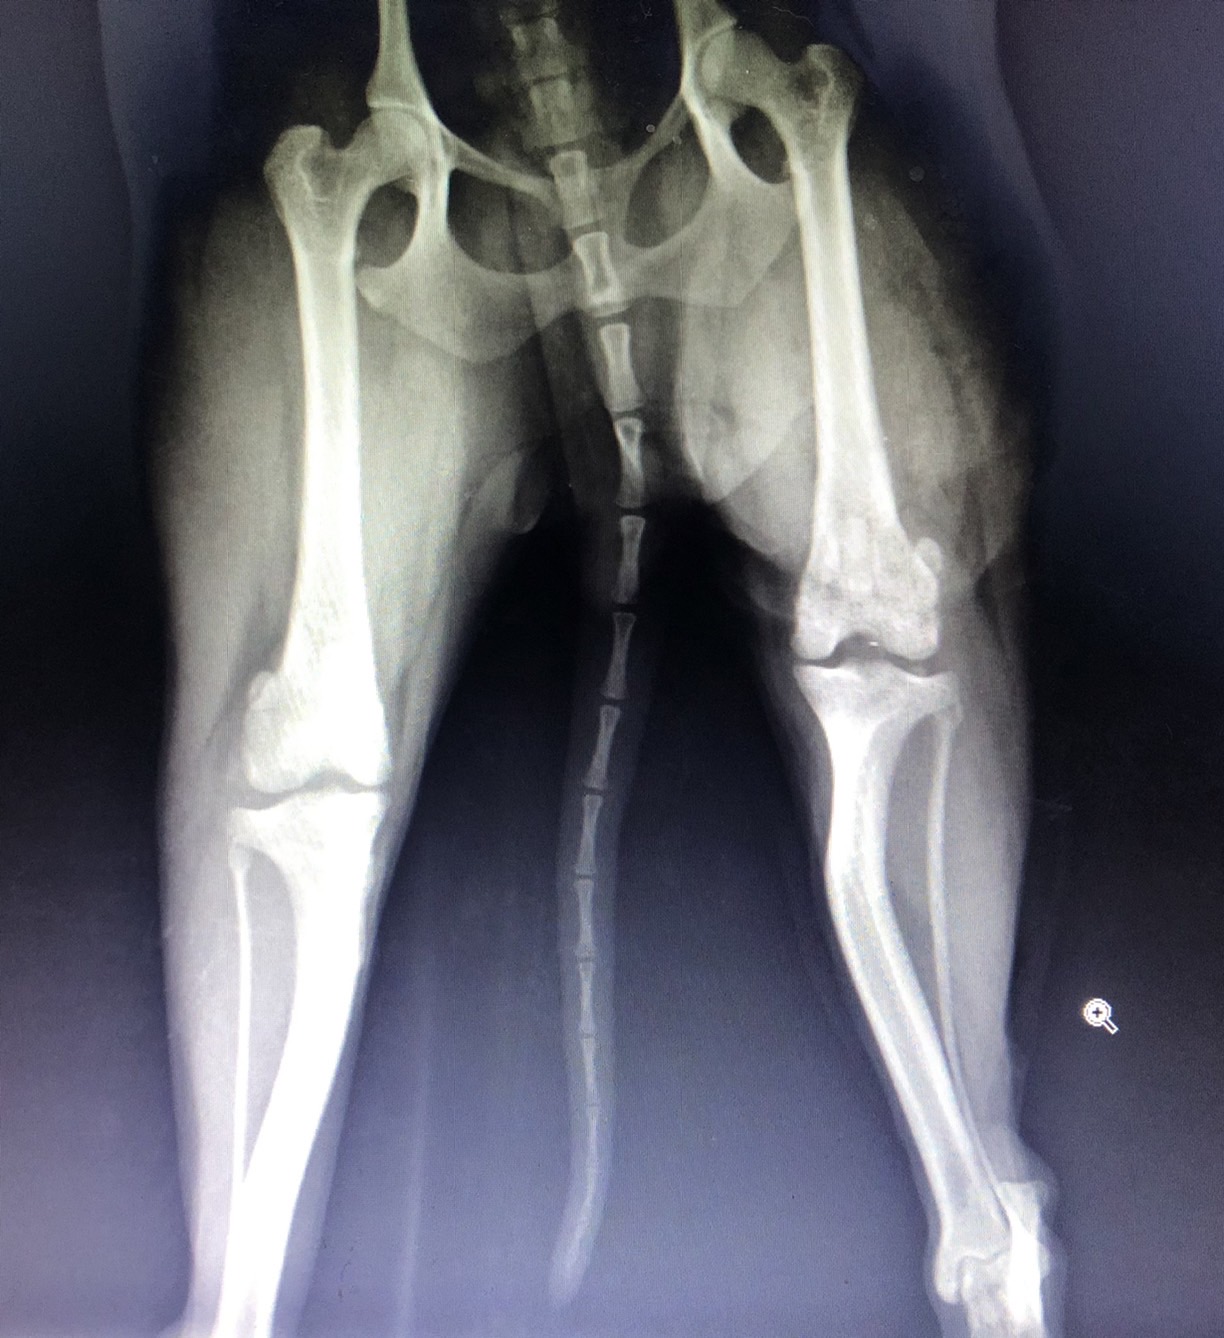

• 脛骨平台水平矯形術

脛骨平台水平矯形術

• ​IVDD 狗狗的椎間盤疾病 4級癱瘓

​IVDD 狗狗的椎間盤疾病 4級癱瘓